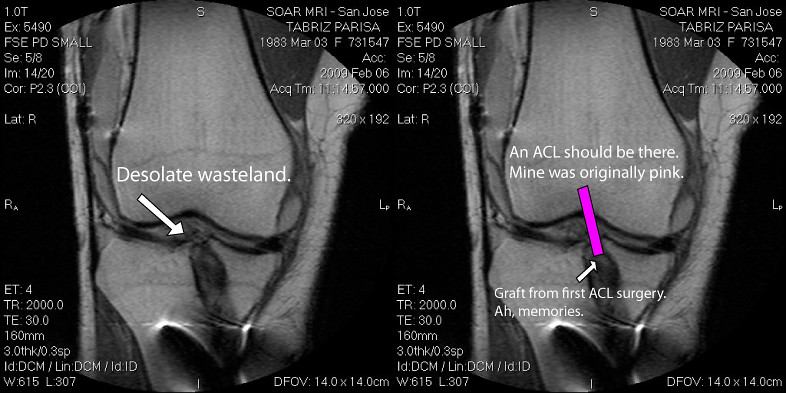

Early intervention is critical. A comprehensive assessment, including clinical exams and imaging (e.g., MRI), confirms the tear’s extent and identifies associated injuries, like meniscus or cartilage damage. This informs your personalized ACL tear physiotherapy services plan, ensuring optimal recovery.